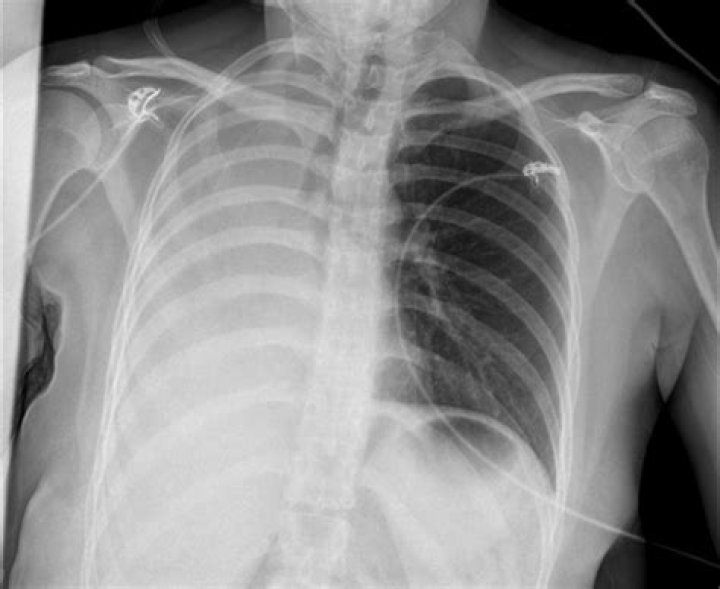

Pneumothorax is the most common complication of transthoracic lung biopsy (4). A patient with stable pneumothorax may be treated conservatively without chest tube insertion. If pneumothorax is large (greater than 30% of hemithorax), is rapidly expanding, or is causing symptoms, chest tube insertion is warranted.

Most studies report a 20% to 25% incidence of pneumothorax after TTNB of the lung, with higher rates when patients have moderate-to-severe emphysema or with core biopsy.

Pneumothorax. The most common complication of chest biopsy is development of a pneumothorax. The largest retrospective series placed the incidence of pneumothorax at 20.5% and the incidence of pneumothorax requiring chest drainage at 3.1%.